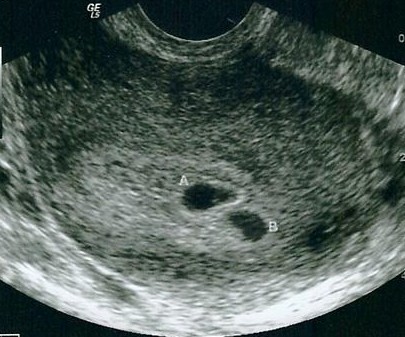

So yesterday I had my first sono, and this is what we saw.........

2 sacs!!!

I really thought my numbers were too low for twins, but I guess I was wrong!!! I go next week to hear the heartbeats!!!

Just wanted to give another update on me. There are now 4 sacs but 3 of them are empty. It looks like baby B split twice, which would've caused identical triplets , but all three quit growing. Good news is we have 1 healthy baby!!! And I finally graduated to my OB! Yay!!! Image Attachment(s):